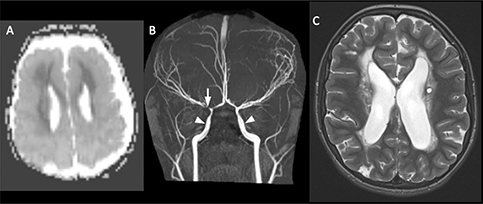

Fig 6

Figure 6. ACTA2 Mutation. Axial ADC (A) demonstrates reduced diffusivity in the periventricular white matter, compatible with acute infarct. 3D Time-of-Flight MRA (B) shows enlargement of the internal carotid arteries (arrowheads) with narrowing of the distal internal carotid arteries (arrow). Follow-up axial T2-weighted image (C) shows evolution of the infarct to cystic encephalomalacia. Case courtesy of Dr. Tamara Feygin, Department of Radiology, Children’s Hospital of Philadelphia.